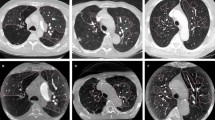

Univariate analysis to determine the predictors of residual hypoperfused segments is shown in Table 2. Among the 212 pre-treatment hypoperfused segments, 42 (19.8%) segments were classified under residual hypo-perfused segment after treatment. The proportion of residual hypoperfused segments was significantly higher in the proximal group than in the peripheral group (26.4% [33/125] vs. 10.3% [9/87], P = 0.004) (Figs. 4 and 5). Vascular patency before treatment was not significantly related to the proportion of residual hyperperfused segments (P = 0.56). Pre-treatment HU values measured on LPBV images were not significantly different between the improved and residual hypoperfused segments (9.156 ± 6.3262 HUs and 9.469 ± 7.567 HUs, P = 0.783). The age and sex ratios were not significantly different (p > 0.05 for both). The interval of CT examinations before and after treatment were significantly different between the improved and residual hypoperfused segments (55.0 ± 78.5 days and 95.1 ± 127.6 days, P = 0.01). Concerning the treatments used, significant differences were observed for thrombolytic therapy (P = 0.012), but none of the other treatments (heparin, warfarin, DOAC, and inferior vena cava filters) were significantly different between the improved and residual hypoperfused segments (p > 0.05 for all).

A 51-year-old-man with pulmonary embolism. (A) Peripheral occlusive thrombi can be seen in left A4a on the pre-treatment computed tomography pulmonary angiography (CTPA). (B) Pre-treatment perfused blood volume shows perfusion decrease in the left S4a. The mean HU value of the segment is 9.0 HUs. (C) Lung perfusion blood volume improved after treatment. The mean computed tomography value of the segment is 37.8 HUs.

A 68-year-old man with pulmonary embolism. (A) Pre-treatment computed tomography pulmonary angiography indicates central occlusive thrombus from the right middle lobar pulmonary artery to A5. (B) Pre-treatment perfused blood volume shows perfusion decrease in right S5. The mean CT value of the iodine map is 11.7 HUs. (C) Lung perfusion blood volume remains decreased even after treatment. Mean CT value of the segment is 10.5 HUs.